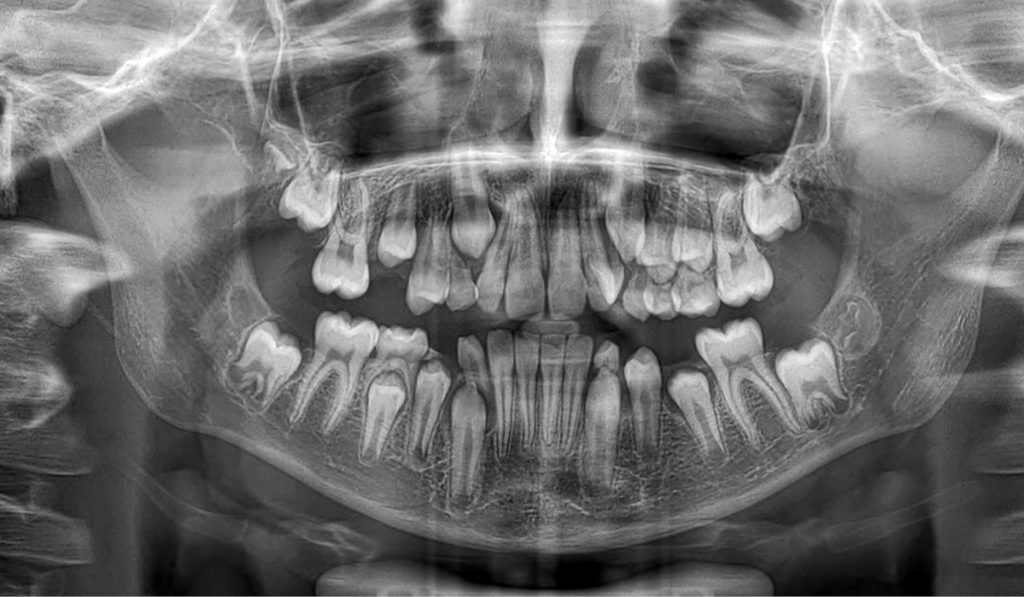

STRESZCZENIE: Występowanie zębów nadliczbowych w okolicy kła szczęki jest bardzo rzadką anomalią zębową. Oszacowano, że stanowią jedynie 1,5% przypadków zębów nadliczbowych. Ich etiologia wciąż pozostaje nieznana. Celem pracy było opisanie przypadku 10-letniego chłopca bez chorób współtowarzyszących, u którego wykryto nadliczbowy kieł w szczęce i wdrożono terapię ekstrakcyjną.

SUMMARY: The presence of supernumerary teeth in the area of the maxillary canine is a very rare dental anomaly. It is estimated that they account for only 1.5% of cases of supernumerary teeth. Their aetiology is still unknown. The aim of the paper is to describe a case of a 10-year-old boy without concomitant diseases in whom a supernumerary canine was detected in the maxilla and an extraction therapy was implemented.